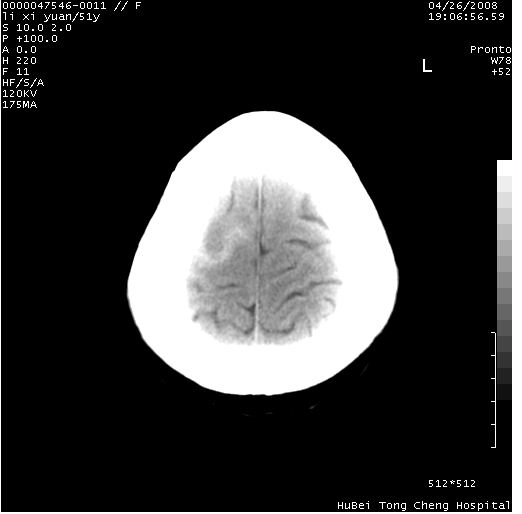

以下是引用余辉在2008-4-27 14:02:00的发言:[br]病灶位于中央沟前方?位于额叶?高密度灶,灶周水肿不明显,病灶似沿脑沟走行,强化明显,局部层面呈现环状强化,考虑1脑表面血管性疾病,如血管瘤,血管扩张,灶内血栓形成,其次考虑肿瘤如脑膜瘤、转移瘤,胶母等

以下是引用形影不离在2008-4-27 14:13:00的发言:[br]考虑胶质瘤可能性大,不排除慢性炎性肉芽肿。建议mri检查。